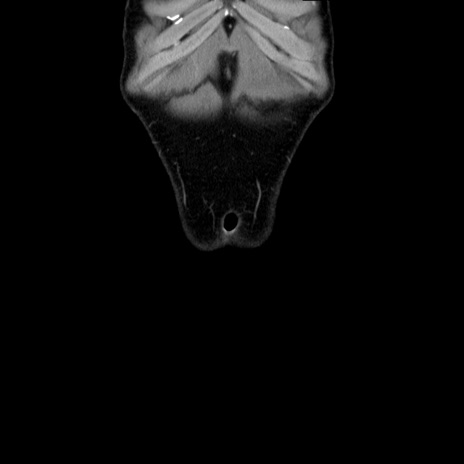

症例36(冠状断像)

【症例】20歳代 男性

【主訴】心窩部痛

【現病歴】今朝より上腹部痛あり。一旦軽快していたが再度出現したため救急要請。昨日夕に白身の魚を含む刺身を食べた。

【身体所見】BP 136/89mmHg、HR 74/min、BT 37.0℃、腹部:膨満、軟、心窩部に圧痛あり。反跳痛なし、筋性防御なし、腸雑音やや亢進あり。

【データ】WBC 17700、CRP 0.48